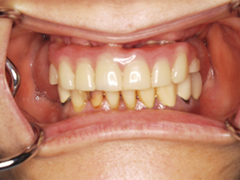

吉本歯科医院では、口内写真とパノラマレントゲンを撮影し、まずは顎の骨の状態まで詳しく確認しました。

院長の吉本の診断は以下でした

・歯周病の進行により歯を支える骨が溶け、歯がグラグラになってきた

・もともとの咬み合わせの悪さ

・合わない総入れ歯を入れていたため骨が退縮している